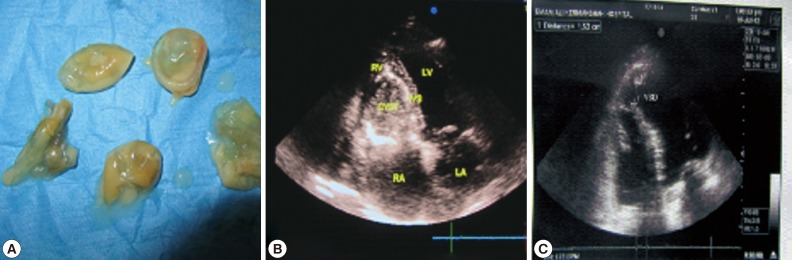

Ameli [11] and Dibello [8] reported that acute coronary syndrome secondary to the compression or emboli to the coronary artery may mimic coronary artery disease. According to Dighiero et al. [12], the resulting pain of pericarditis may radiate to the epigastrium and, it may closely mimic acute abdomen. Uysalel et al. [13] reported that a case of myocardial hydatid cyst mimicked left ventricular aneurysm. Other complications included mitral regurgitation (MR), papillary muscle ischemia, atrioventricular conduction defects. Arrhythmia was also report in a study by Agarwal et al. [10]. In the present study, we encountered a 44-year-old male patient with hydatid disease in the intraventricular septum of the heart with papillary muscle involvement and clinical symptoms of dyspnea and chest pain. The preoperative diagnosis was established using echocardiography and confirmed after recovery of hydatid daughter cysts (Fig. 1A).

A 46-year-old man non-smoker was admitted to our hospital due to dyspnea and chest pain for the last 4 months that exacerbated some days before admission. He did not complain of any other symptoms. He gave exposure to dogs and having reared sheep. The physical examination revealed no specific findings except precordial systolic souffle. Lung auscultation revealed a normal intensity of breath sounds. Electrocardiogram (ECG) did not show any remarkable findings except for right bundle branch block (RBBB). All routine laboratory test results, including liver and kidney function tests, serum proteins, and urine analysis were normal. The erythrocyte sedimentation rate was abnormal (ESR 60 mm/hr). Serology for echinococcosis showed an indirect immunohemagglutination test positive. Chest x-ray was normal. The computed tomography (CT) scan of the abdomen and thorax showed no disease. Transthoracic contrast echocardiography revealed a huge cyst like a hypodense structure (65×55 mm), located in the interventricular septum and the base of papillary muscle with distortion of mitral wall apparatus (i.e., papillary muscles) and moderate MR (Fig. 1B). The rest of examination was normal with an estimated ejection fraction of 45%, without regional wall motion abnormalities. Coronary angiography revealed normal coronary arteries.

The patient underwent median sternotomy, and excision of the cardiac cyst was planned by using cardiopulmonary bypass. The patient received albendazole preoperatively with the dose of 800 mg daily for 2 weeks. After a median sternotomy, the patient was connected to the cardiopulmonary bypass by cannulating the ascending aorta and superior and inferior vena cava. There was no sign of pericarditis, and pericardial cavity was free of fibrosis and adhesions. Under a condition of hypothermic cardiopulmonary bypass, the aorta was cross-clamped and the heart was arrested with a dose of antegrade cold cardioplegia. The right atrium was opened that revealed bulging of the septum that was calcified as a white and hard mass in the right ventricular aspect of the septum (Fig. 1C). The pericardial cavity was localized by pad moistened by ethanol 96%, and 10 ml ethanol was injected to the cyst cavity and after 5 min non-viscous yellow painted fluid was aspirated. A large incision was made into the right ventricular aspect of the septum corresponding to cyst's free wall.

The sub-septal wall of the cyst was calcified, fibrotic, and was not excised but its contents included the glistening germinative layer and daughter cysts were sucked out (Fig. 1A), which were sent to histopathological examinations (Fig. 2A). The cyst was then washed with 5 ml of povidone iodine solution, which was left inside for 5 min and then aspirated. The resultant cavity made by intraseptal partitioning was then obliterated by approximation of its fibrosis walls with 4-0 viline suture to complete this obliteration. We explored the left ventricle via the left atrium that revealed involvement of the base of huge anterior papillary muscle as a subsidiary horn. The muscle was opened at its medial aspect in conjunction with the septum. The residual hydatid cyst, which contained membranes and daughter vesicles, was removed. The remaining cavity was left open. The septal involvement by the cyst caused distortion of the mitral apparatus by papillary muscle elongation. Anterior mitral leaflet prolapse that has normal segment of the P1 and P2 scallops were repaired by means of corda tendina shortening.

Pathological examinations of the daughter cyst and fluid revealed germinative layers (Fig. 2A). Normalized lengthening of the papillary muscle and corda tendina eliminated moderate MR post-operatively. After operation, transesophageal echocardiography revealed a venticule septal defect (VSD) in the base of the anterior papillary muscle which was repaired with 4-0 viline sutures (Fig. 2B). The patient had an uneventful recovery and at the 7th postoperative day she was discharged from the hospital with an acceptable echocardiography findings which revealed near normal functions of the mitral valve apparatus, with only mild regurgitation.